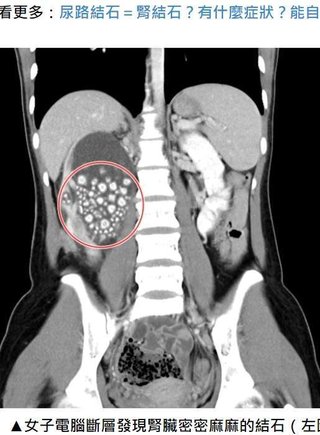

グロ注意「水をほとんど飲まなかった20歳女性の腎臓から300個以上の結石を回収(台湾)